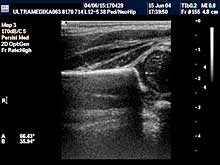

- Arteriska hipertenzija

Povišen pritisak može biti prisutan i u dečijem dobu. Radi

otkrivanja uzroka arterijske hipertenzije savetuje se obavezan

Ultrazvučni pregled bubrežnih-renalnih arterija. Pregled podrazumeva

kompjutersko kodiranje kolorom protoka kroz renalne arterije nakon

njihovog ovajanja od aorte ili u samim bubrezima. Na ovaj način se

određuje brzina protoka I kvalitet dobijenih Doppler krivulja

intrarenalnih arterija. Ovakva ultrazvučna dijagnostika može otkriti

klinički značajno suženje bubrežne arterije koje je odgovorno za

povišen pritisak. Registrovanje protoka je često nemoguće ranijim

konvencionalnim ultrazvučnim aparatima. Medjutim, danas savremena

tehnologija broad band kolor-Dopplera i CPD čini ovaj pregled

mogućim.